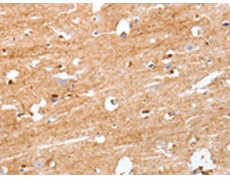

IHC positive control: |

Human brain |

IHC Recommend dilution: |

25-100 |